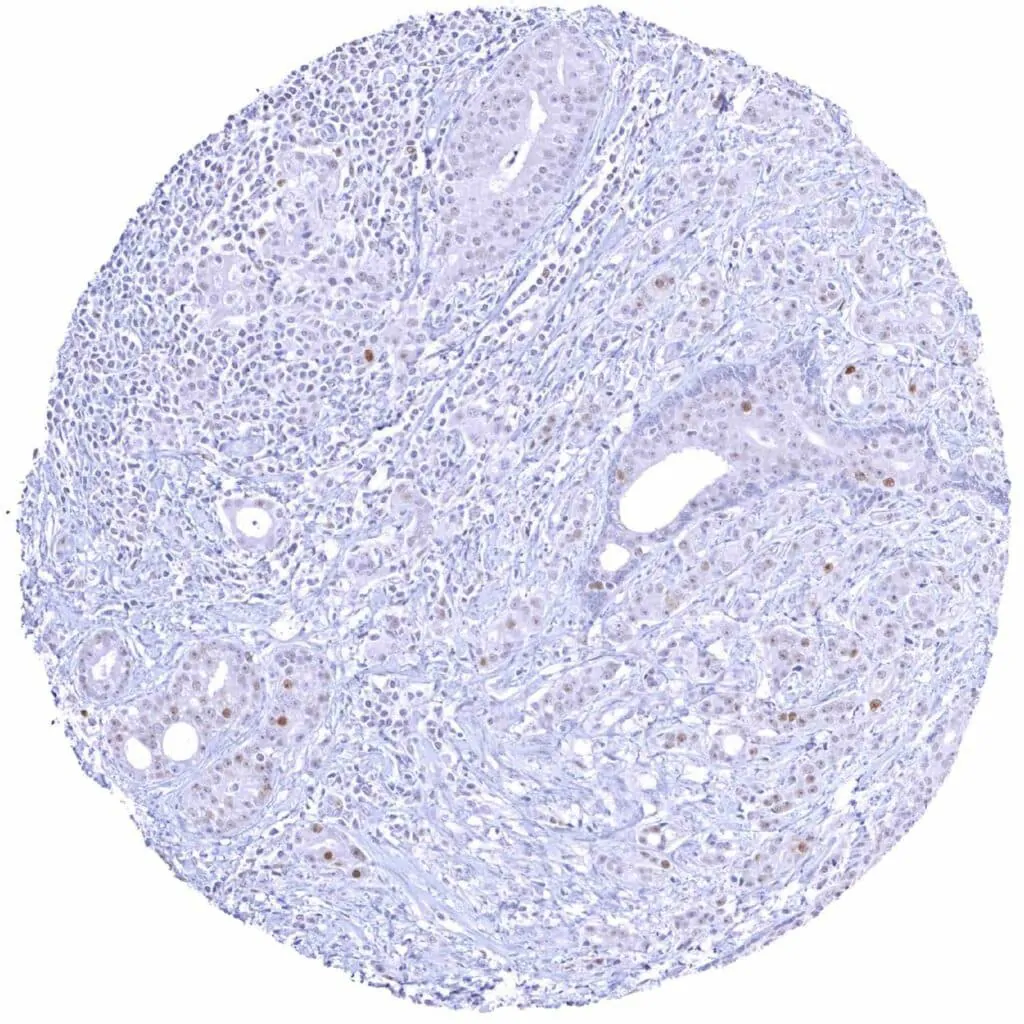

Prostate – Adenocarcinoma (Gleason 3+3=6) showing a weak Cyclin E1 positivity of a small fraction of tumor cells